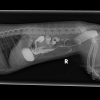

ديروز من بردمش دكتر و اونا نظرشون اين بود كه ممكنه چيزي قورت داده باشه و توي شكمش گير كرده باشه. سوفي xray شد و گفتند مقدار زيادي گاز توي شكمش هست، بهش berim contrast دادن و يكساعت بعد دوباره xray گرفتن و فقط مقدار كمي از كانترست خارج شده بود كه ميگفتن طبيعي نيست بايد خارج ميشده، صبح باز هم xray شد و بيشتر كانترست خارج شده بود ولي ميگفتن چون هنوز كمي اش مونده ممكنه چيزي باشه و بايد عمل بشه، اما من هنوز متقاعد نشدم، آيا واقعا اگه چيزي بود نبايد توي سه بار عكس گرفتن اونم بعد كانترست نباد نشون بده؟ سوفي بينهايت آب بدنش كم شده و واقعا نياز به سرم داره، ديگه بالا نياورده اما تا ديشب اسهال داشت. اونا بيست و چهار ساعت براي عكس نگهش داشتن تازه امروز گفتن بايد بيست و چهار ساعت ديگه بمونه براي سرم، اينجوري من فقط شارژ ميشم بدون اينكه مطمئن باشم قضيه چيه و اين كوچولوي زبون بسته هم هنوز حالش خوب نيست، من جواب ها رو براتون ايميل ميكنم، اگه نظرتون رو بگيد واقعا مديونتون ميشم.